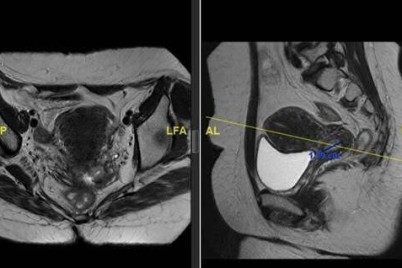

الرياض - منيفة الشمري تمكن فريق طبي في مدينة الملك فهد الطبية إحدى مكونات تجمع الرياض الصحي الثاني من...